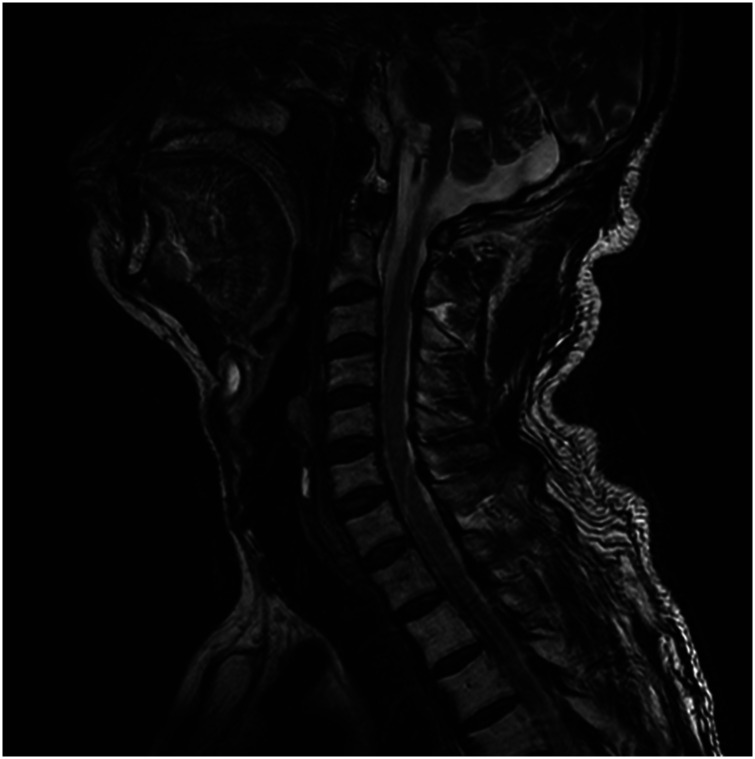

颈神经根病的发病率约为85 / 100000,其特点是颈神经根断裂引起疼痛。由于缺乏普遍接受的黄金标准,准确诊断具有挑战性,需要依赖患者病史、临床检查和诊断测试。臂丛神经转移是一种罕见但临床意义重大的疾病,可以模仿常见的肌肉骨骼疾病,如颈椎神经根病。其非特异性表现往往导致诊断延迟,特别是在癌症患者表现为持续上肢疼痛。本病例报告探讨了锁骨上臂丛转移的误诊,最初被误解为颈椎间盘突出,62岁男性肺癌病史。尽管接受了颈椎导管神经成形术和其他治疗,但患者持续的右臂疼痛促使进一步的调查。胸部计算机断层扫描和正电子发射断层扫描最终显示转移性鳞状细胞癌延伸至臂丛。该病例强调了对有癌症病史的患者进行全面诊断评估和考虑转移性肿瘤的关键需要。这也凸显了臂丛转移的罕见性和临床意义。它强调了综合护理方法的重要性,解决肿瘤和肌肉骨骼问题,以改善患者的预后。

Cervical radiculopathy, with an incidence of approximately 85 per 100,000 individuals annually, is characterized by pain originating from cervical nerve root disruption. Accurate diagnosis is challenging because of the absence of a universally accepted gold standard, necessitating reliance on patient history, clinical examination, and diagnostic tests. Brachial plexus metastasis is a rare but clinically significant condition that can mimic common musculoskeletal disorders, such as cervical radiculopathy. Its nonspecific presentation often results in delayed diagnosis, particularly in patients with cancer presenting with persistent upper-limb pain. This case report explored the underdiagnosis of supraclavicular brachial plexus metastasis, initially misinterpreted as cervical disc herniation in a 62-year-old man with a history of lung cancer. Despite undergoing cervical-Racz catheter neuroplasty and other treatments, the patient's persistent right arm pain prompted further investigations. Chest computed tomography and positron emission tomography computed tomography ultimately revealed metastatic squamous cell carcinoma extending to the brachial plexus. This case underscores the critical need for comprehensive diagnostic evaluations and the consideration of metastatic neoplasms in patients with a history of cancer. It also highlights the rarity and clinical significance of brachial plexus metastasis. It emphasizes the importance of an integrated approach to care, addressing both oncological and musculoskeletal issues to improve patient outcomes.